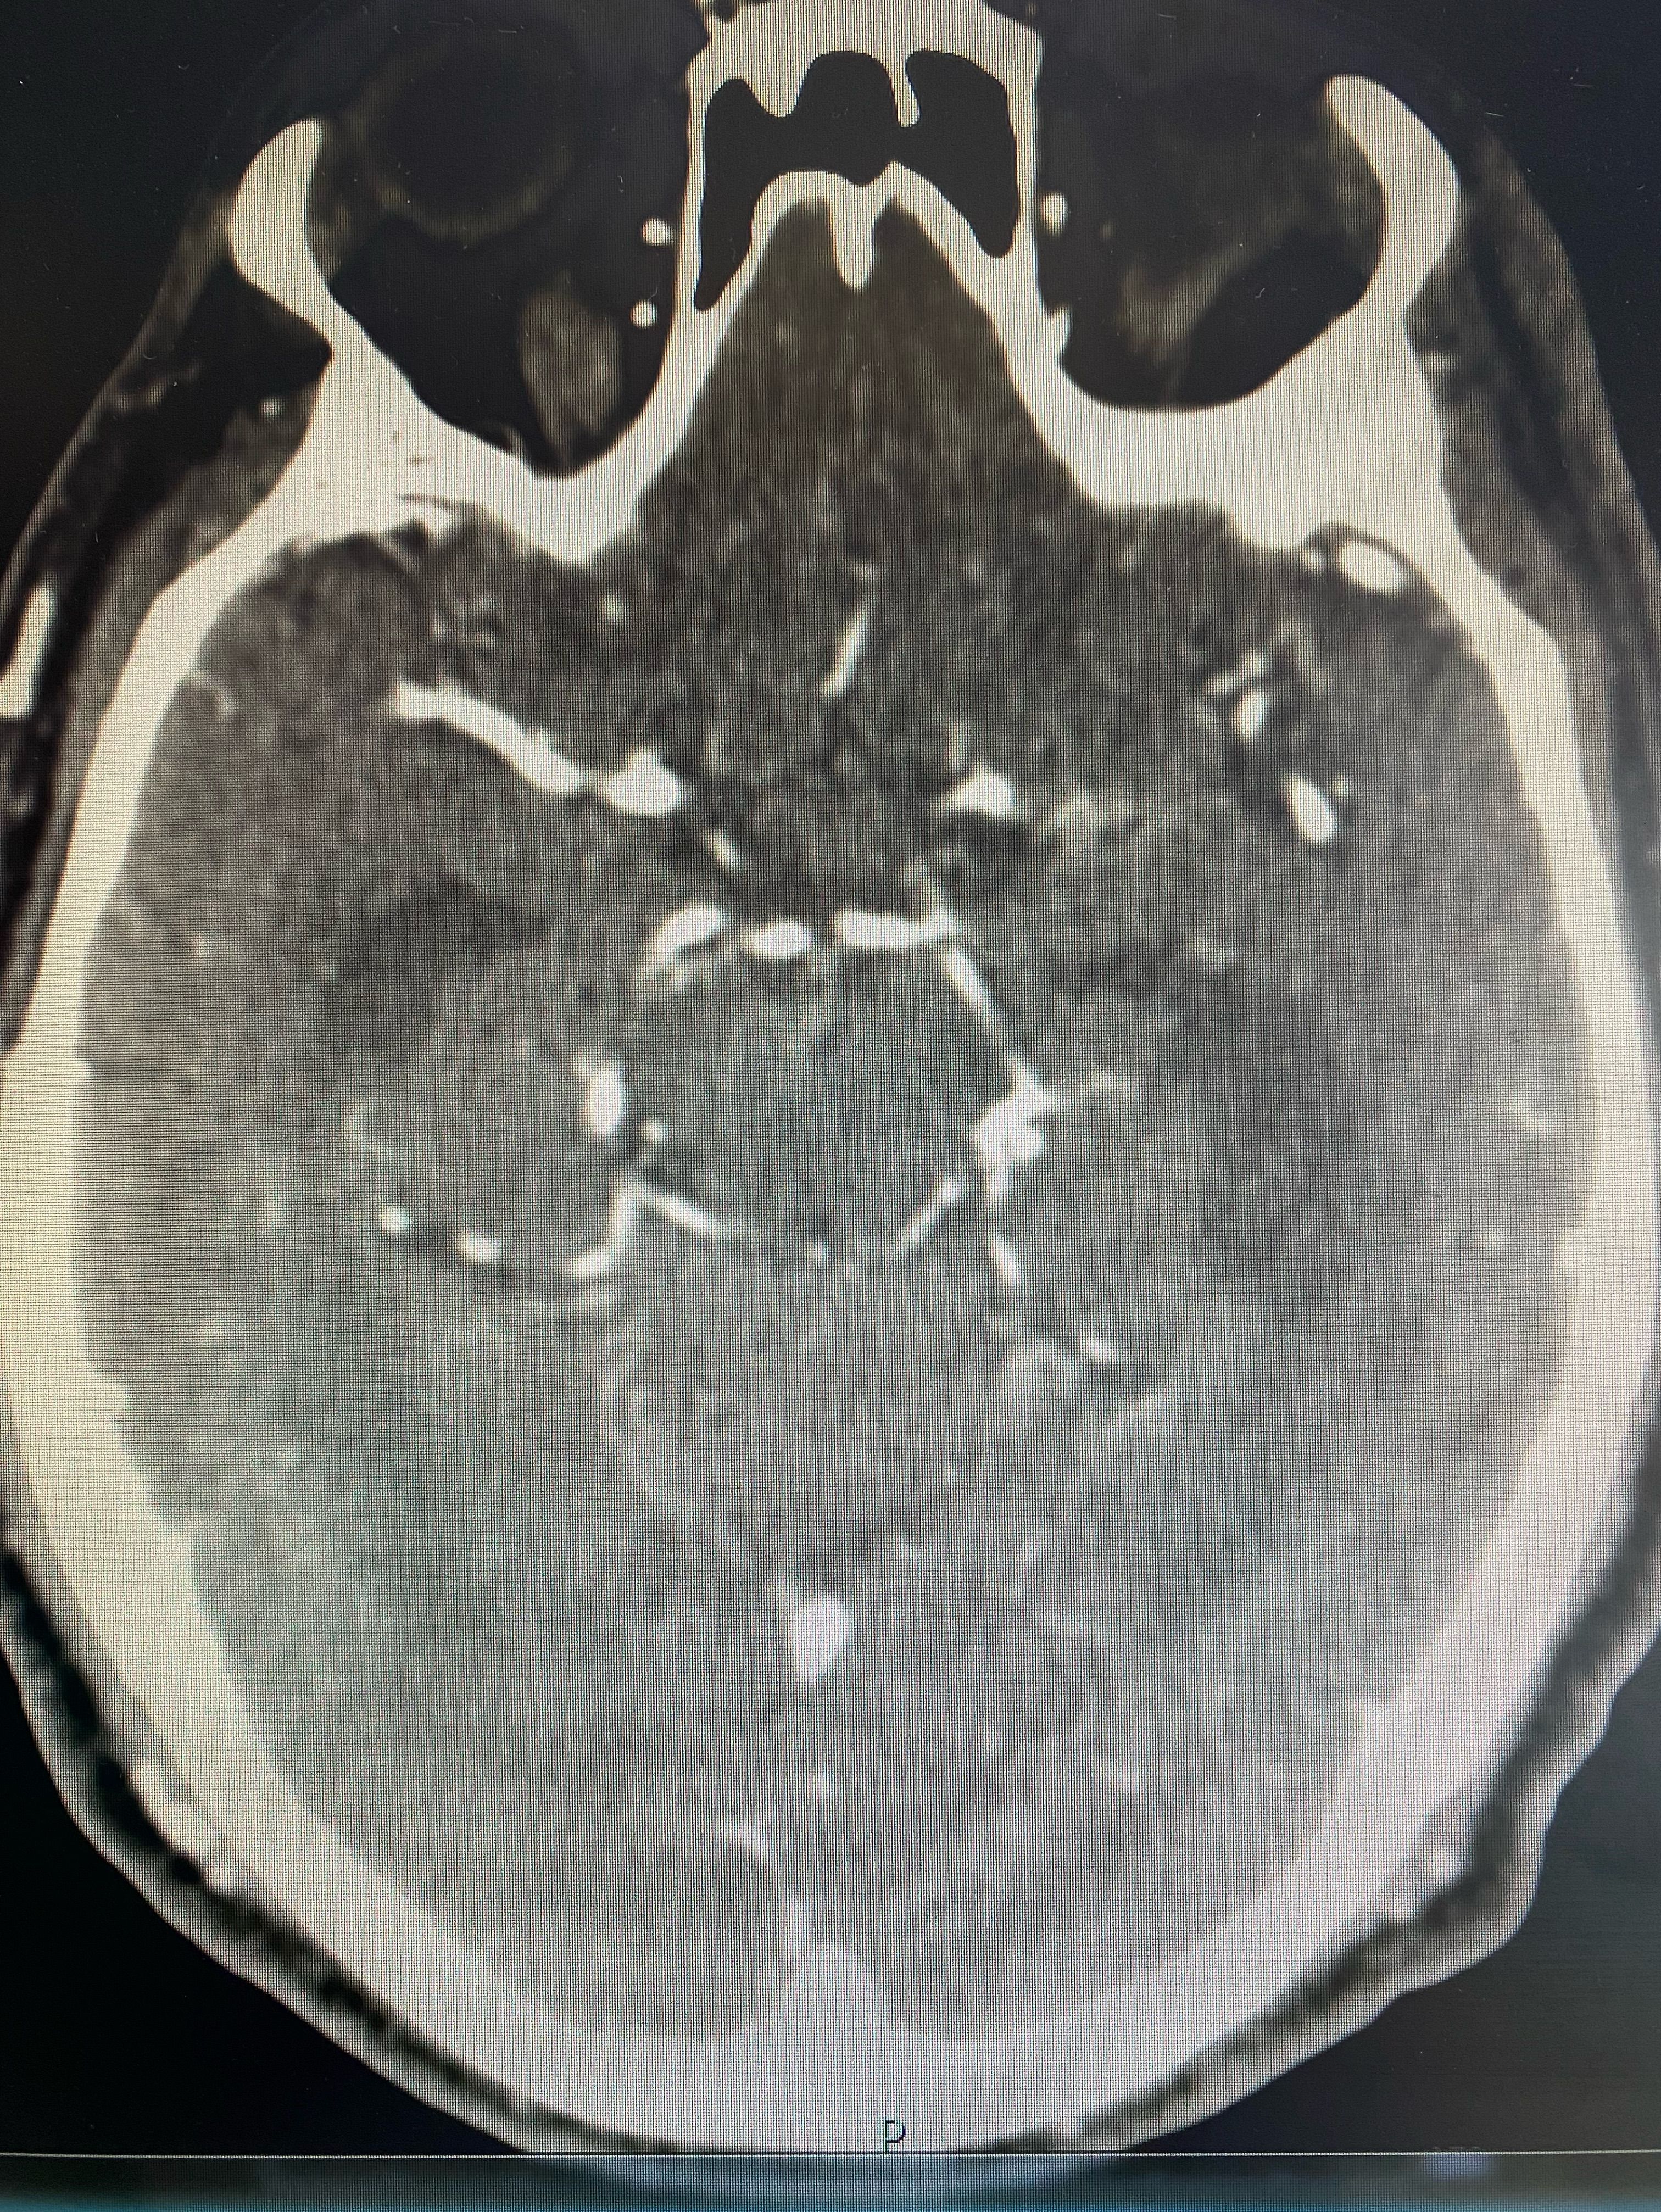

Circle of Willis on CT scan

Imaging

Ctscan

Circleofwillis